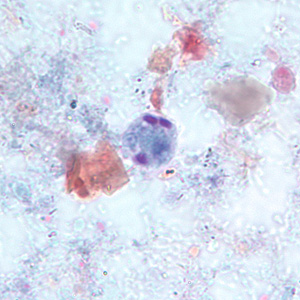

Dientamoeba fragilis

binucleate (two nucleus) with a fragmented karyosome